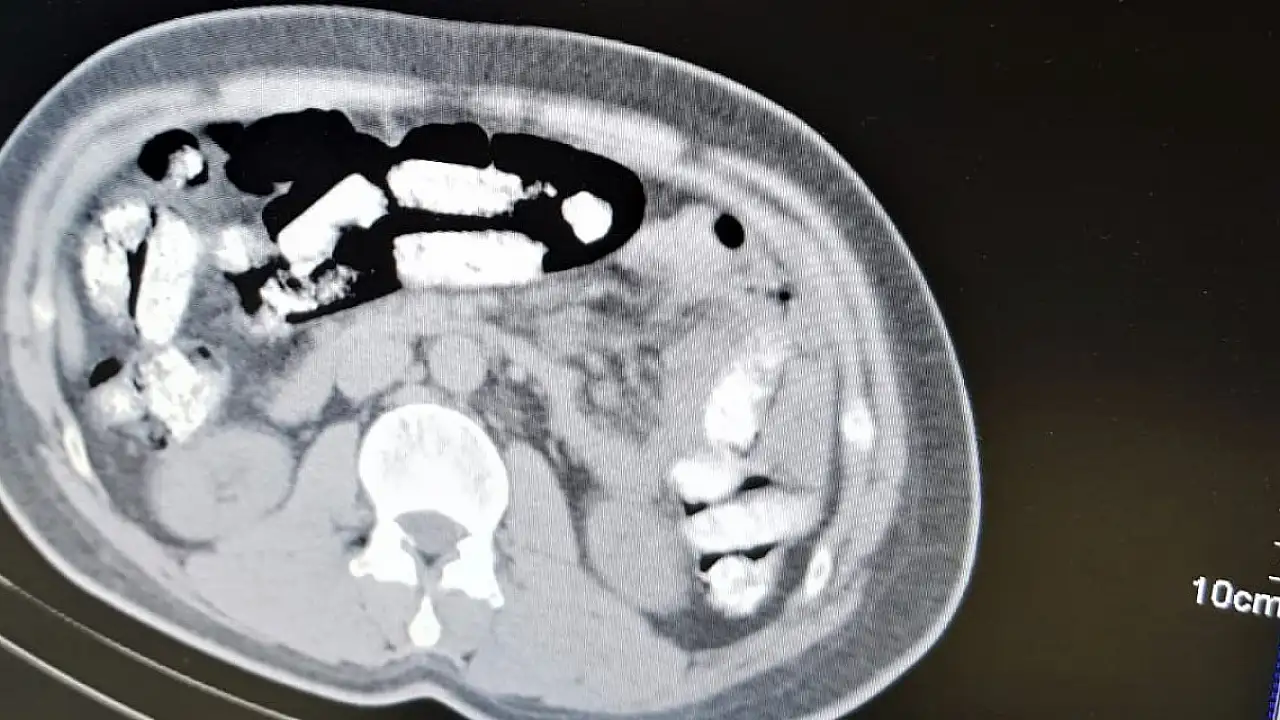

Erzincan İl Emniyet Müdürlüğü Narkotik Suçlarla Mücadele Şube Müdürlüğü ekiplerince uyuşturucu madde kuryeliği yapan şahıslara yönelik İran otobüsleri üzerinde yapılan uygulamada; İran otobüsünde yolculuk yapan Abdulmennan S. isimli İran uyruklu kişinin yutma yöntemiyle uyuşturucu taşıdığı değerlendirilmesi üzerine, Erzincan Mengücek Gazi Eğitim ve Araştırma Hastanesinde zanlının bedeninden 106 fişek halinde toplamda 1 kilo 198 gram Afyon Sakızı ele geçirildi. Abdulmennan S. hakkında TCK 188 suçundan yapılan tahkikat sonrası sevk edildiği mahkemece tutuklanarak cezaevine teslim gönderildi.